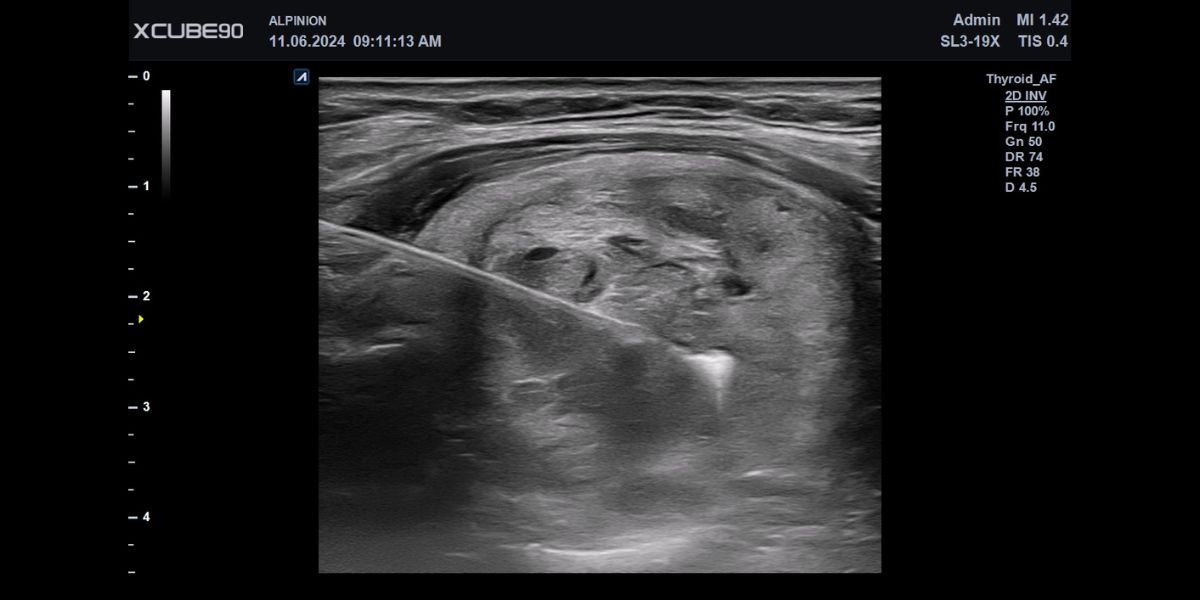

Najlepszy ultrasonograf do USG twarzy w medycynie estetycznej.

Coraz więcej procedur medycyny estetycznej wymaga wykonania badania USG twarzy, (lub dokładniej USG tkanek miękkich twarzy). Badanie USG skóry twarzy w gabinecie medycyny estetycznej gwarantuje bezpieczeństwo nie tylko pacjentów, ale również osoby wykonującej dany zabieg. Ponieważ liczba wykonywanych procedur…